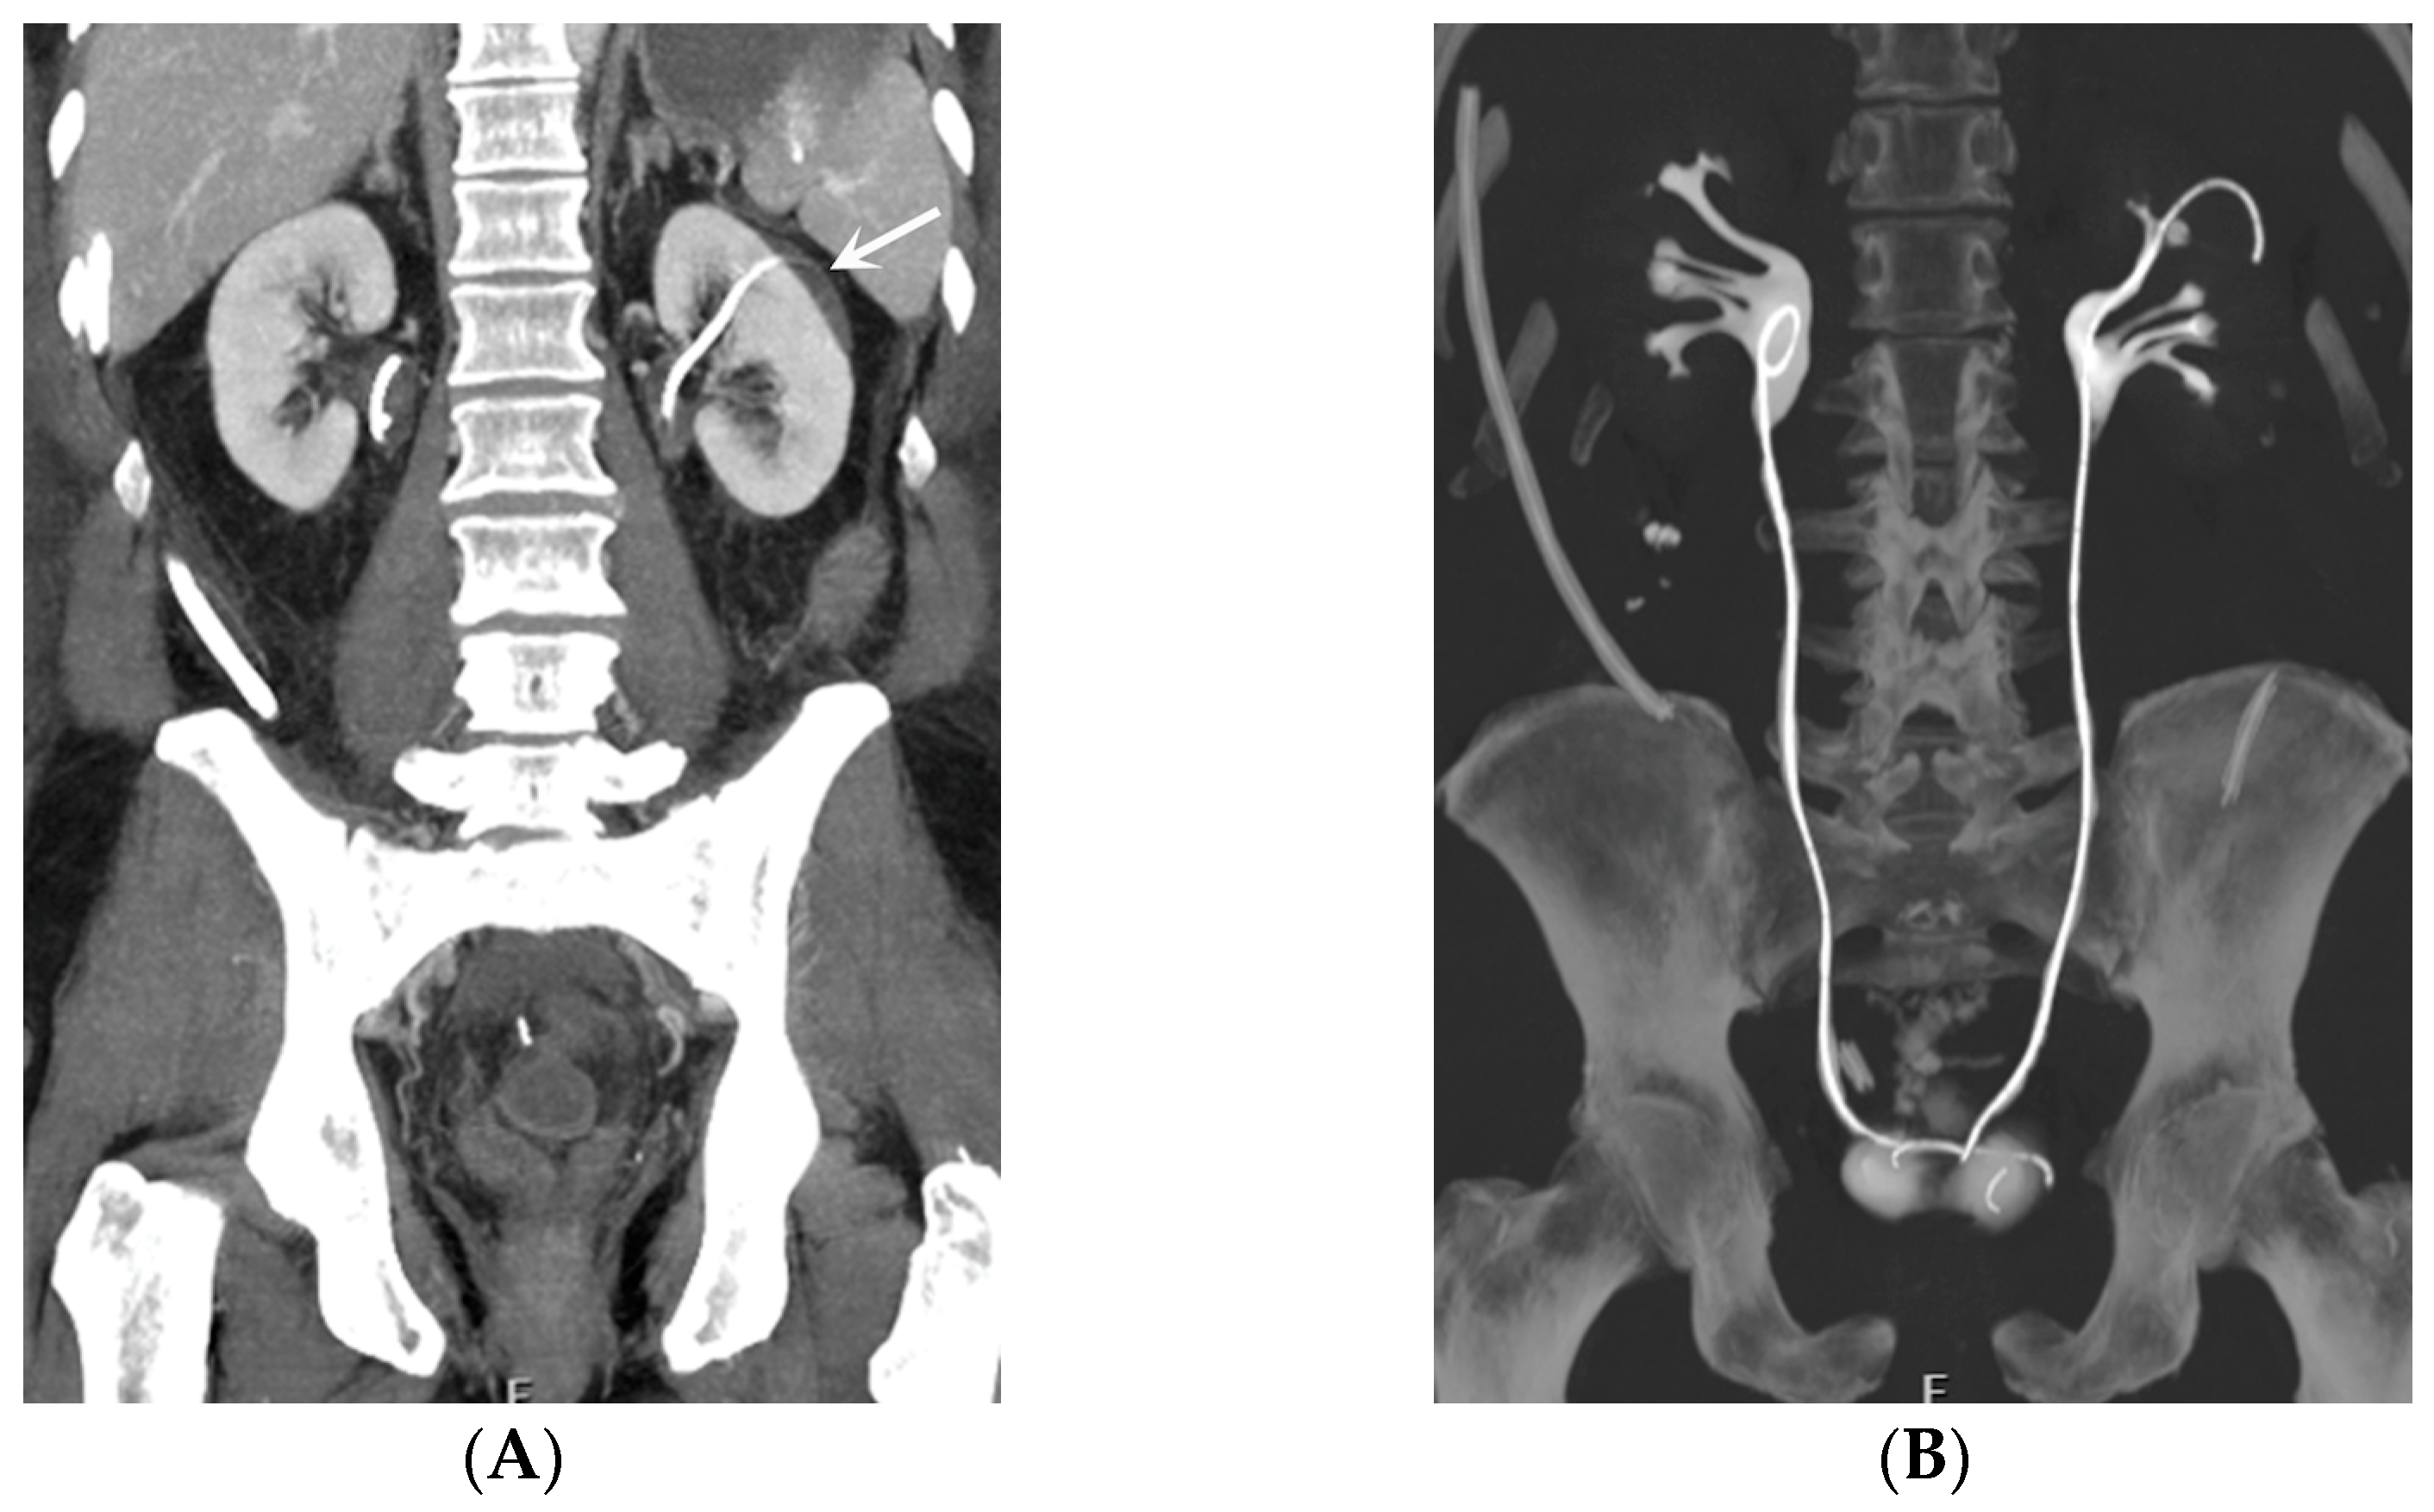

- Malposition: The malposition of a stent is defined as an incorrect position relative to initial placement, while displacement presents a subsequent occurrence in a device that was previously located in the correct position. A stent improperly positioned might assume a sub-pyelic position when the proximal end fails to reach the renal pelvis and a supravesical position when the distal end is detected within the ureter. The origins of this complication predominantly stem from the placement technique, whether it be endoscopy- or fluoroscopy-guided insertion. This underscores the need to verify the accurate positioning of the stent post-placement. Ensuring an adequate length is essential to reduce the occurrence of this complication (Figure 2, Figure 3, Figure 4, Figure 5 and Figure 6) [21,22].

- Stent Knotting: It is a rare complication. Most of these knots involve the proximal end of the stent near the coil, but every portion can be affected [27,28]. Previous reports have attributed knot formation to the excessive length of the stent, stent shape (double-J or multicoil), and flexibility or anatomical abnormalities, such as cystocele and ileal conduits. An abdominal X-ray and, especially, a CT scan are more sensitive than other imaging modalities in identifying a ruptured or knotted stent as well as its migration (Figure 7) [29,30].